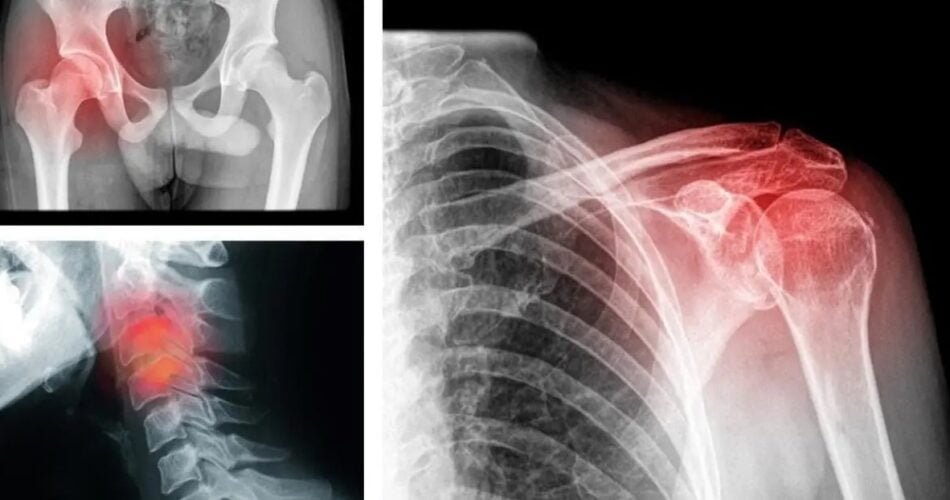

9 types de douleurs physiques provoquées par nos états émotionnels :

3 – Douleur aux épaules

Qui n’a pas mal à l’épaule après avoir été trop chargé? En fait, ce fardeau peut être à la fois physique et émotionnel. Ne laissez pas vos questions être submergées, discutez-en et partagez-les avec les gens autour de vous pour apaiser vos inquiétudes. Par conséquent, vous réduirez le fardeau et soulagerez la douleur.

8 – Douleur aux hanches

Cette douleur survient parce que vous avez peur d’avancer. Il vous est difficile de prendre des décisions dans l’actualité. Vous restez vigilant, vous inquiétez des changements à venir. Par conséquent, il est temps de rassembler le courage de vous armer et de vous libérer de tout ce qui ralentit le développement et entrave sa progression.